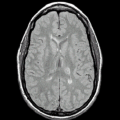

Figure 2: Images displayed at fixed gray level windows. Original images (first row), images after intensity standardization (second row). In each row, a slice from the PD studies of three MS patients is displayed.

Figure 3: Slices from a standardized FSE PD, T2 study pair (left images of rows 1 and 2), the corresponding slices from the scenes depicting the fuzzy affinity relations for the GM, WM, and CSF objects (first row), the same slices from the scenes depicting the connectedness values (second row), and the hard (binary) segmented objects (third row). Binary mask for brain parenchyma is shown in the botom left image.